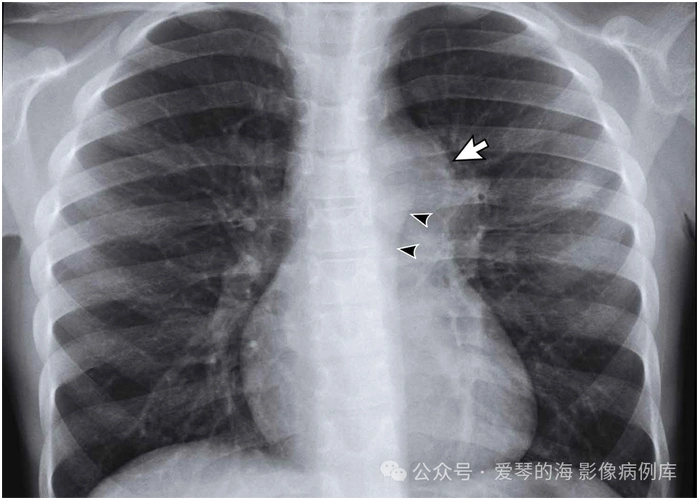

肺结核:活动性,还是非活动性?